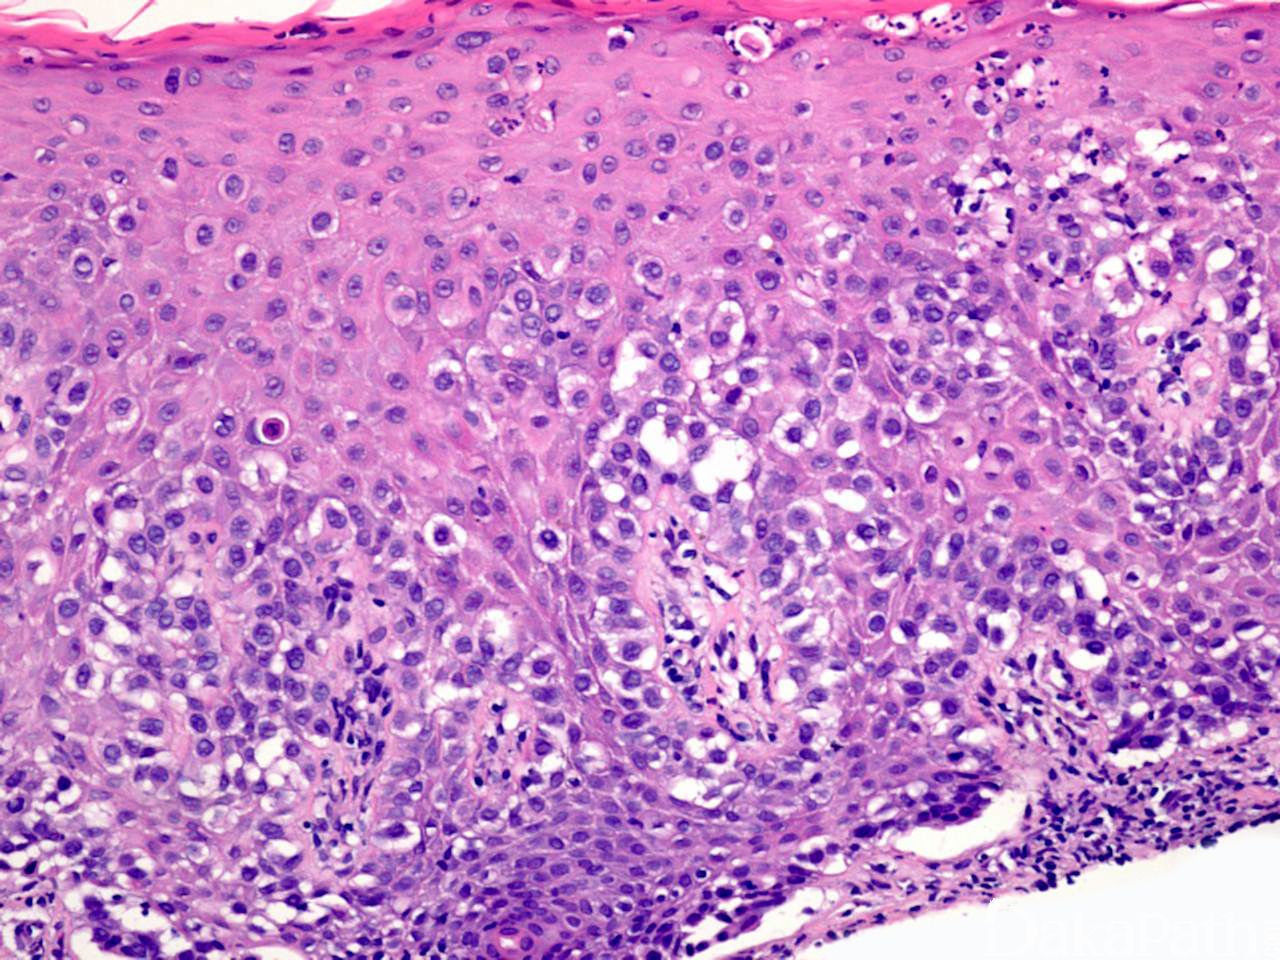

组织学特征性地表现为表皮内非典型上皮细胞单个散在或成群分布于上皮各层内,有时可形成导管或腺样结构;

细胞体积大,胞质淡染、内含黏液或透亮,有时可伴有黑色素颗粒;

Paget 细胞间常见裂隙样结构;

表皮可显著增生。